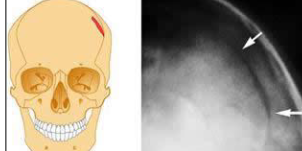

What type of fracture is this?

Depressed fracture

common in middle/older age